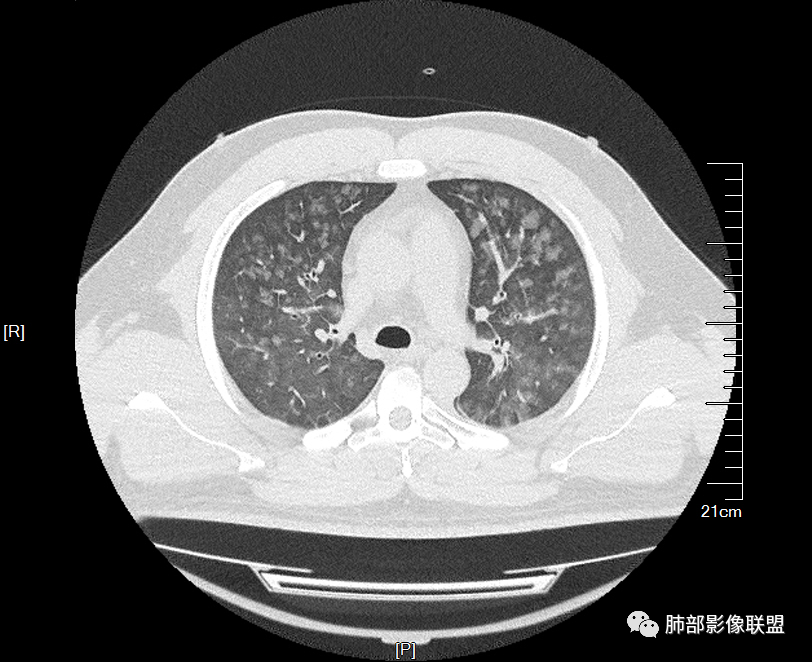

双肺多发弥漫性磨玻璃结节影,大小不一,形态不规则,部分融合,支气管未见明显扩张,部分血管束略增粗,叶裂胸膜增厚,临床有痛风,左足痛6天,考虑:1:痛风结节(一般实性结节,很少磨玻璃结节影)2:血管炎?3:病毒性肺炎(水痘-疱疹肺炎?)

双肺多发腺泡结节及磨玻璃,小叶间隔增厚(大网格状),腺泡结节内及磨玻璃内可见细网格影(小叶内间隔增厚),影像表现符合肺泡出血改变,血肌酐升高,考虑肺肾综合征。鉴别肺水肿。

两肺弥漫向心分布的腺泡结节,部分融合,两肺小叶间隔增厚,血肌肝高,考虑肺泡性肺水肿

年轻男性,痛风史,高血压史,肌酐高,左足痛6天入院。胸CT:双肺多发弥漫性磨玻璃结节影,大小不一,部分融合,上中下肺都有,中内带多,胸膜下少。部分血管束略增粗,小叶内间隔、小叶间隔增厚,下肺明显,左室大。叶裂胸膜增厚。临床有痛风,左足痛6天,考虑:心衰、间质性肺水肿?弥漫性肺泡出血?鉴别:MPA,肺肾综合征,痛风结节等。

多发GGO结节,边界清,以全小叶、小叶中心为主:

小叶间隔增厚,无明显重力趋势

中轴间质稍增厚

细网格也明显

中轴间质增厚,小叶间隔增厚,小叶内间质增厚,部分重力作用,双侧对称,胸水,按理淋巴道回流受阻有

肺水肿类病变有

问题是腺泡结节如何解释?

一般吸入性病变,肺泡腔充填性病变